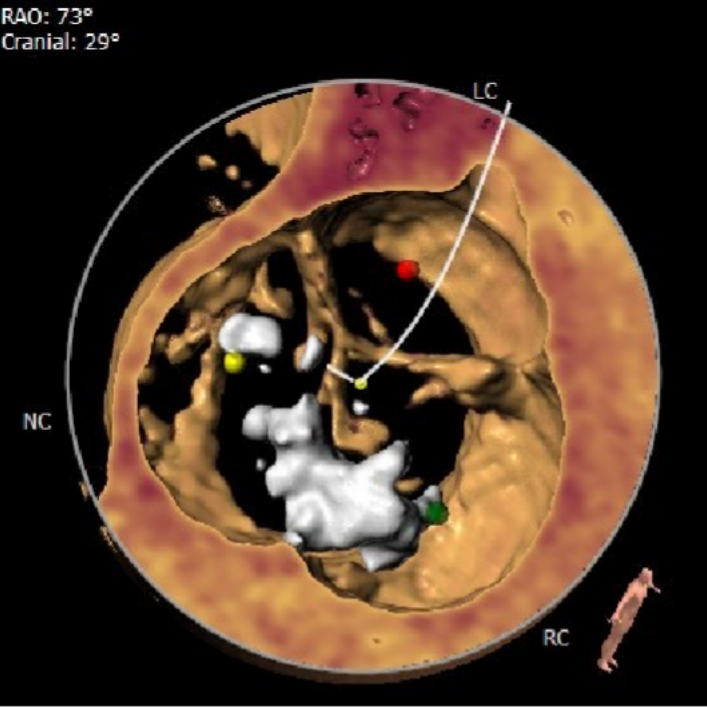

该患者为一例重度AS患者。Type1型二叶式主动脉瓣,瓣叶重度钙化并明显纤维增厚,右、无冠瓣融和成团块状钙化嵴,钙化灶分布不均匀,瓣口形状差,呈火山口状。假体瓣膜释放后有位移可能。

CT数据显示该患者为Type1主动脉瓣。

主动脉瓣瓣环周长80.8mm,平均周长径 25.7mm,SOV:34.8mm*34.3mm*33.4mm,瓣叶增厚,瓣上见右无钙化嵴,瓣环水平夹角42°。